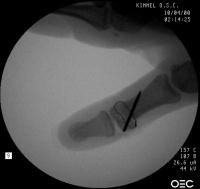

Intraoperative fluoroscopy. The mass:

Click for larger image

Osteotomy planning: proximal pin parallel to the proximal joint line, distal pin parallel to the distal joint line:

Pins were used as saw blade alignment guides:

Osteotomy closed:

Intraosseous wire passed through pin tracts, interfragmentary pin: